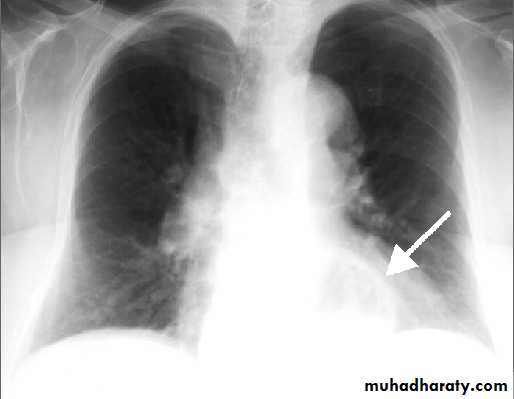

Lingular consolidation-PA. Patchy effacement of the left heart border.

Left upper lobe consolidation-Lat.

The opacification is sited anterior to the obliq- fissure-the position of the upper lobe.RLL collapse - PA.